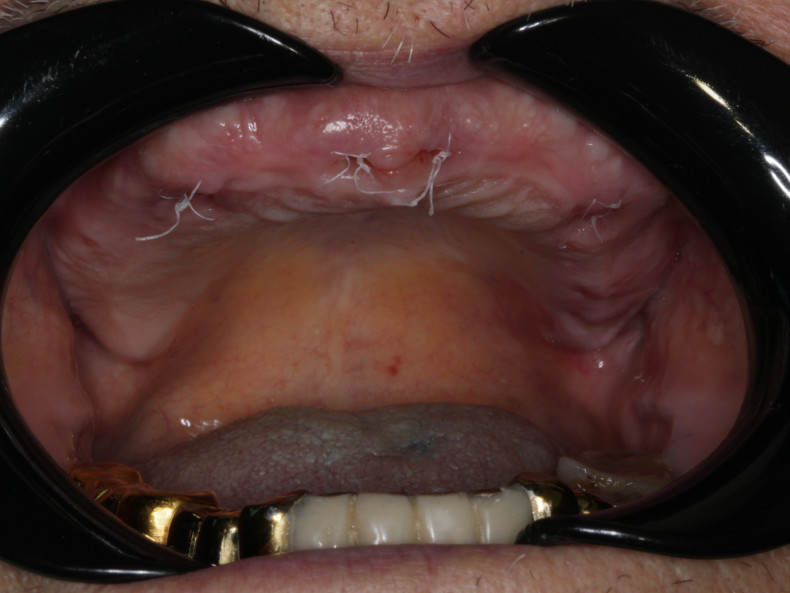

Предоставление стоматологических услуг по ортопедической стоматологии (виниры, коронки циркониев с нанесением микрокерамики, металлокерамические конструкции, циркониевые протезы на имплантах, акриловые и нейлоновые протезы). Услуги по имплантации и удалению зубов и пластика мягких тканей.